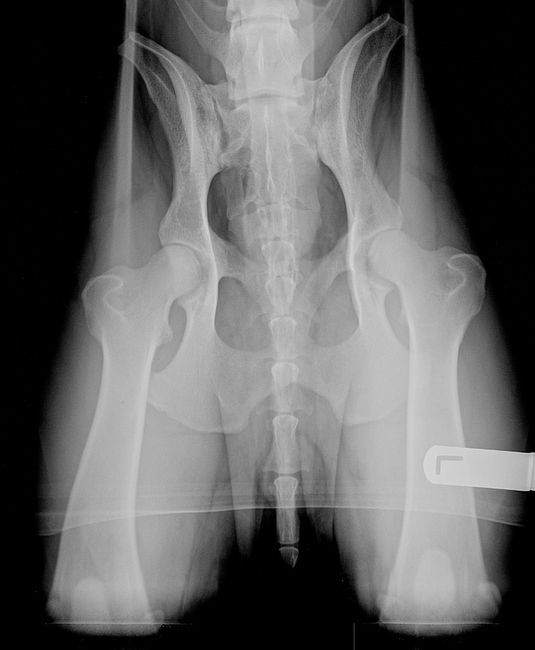

Ik kijk net even in mijn mailbox en ik heb de fotos, hier zijn ze.

Eros zijn rug foto, als je de donkere lijn volgt naar zijn staart zie je dat dan een knik komt, dat is de wervel die niet goed staat.

Alleen zie je de knik niet zo, anders maar even in mijn foto map kijken dan kan je de foto vergroten en beter zien.

De hond ligt n.l. behoorlijk scheef, de (rechts op de foto)kop en kom liggen niet op een lijn, en de rechterkop is veel kleiner dan de linker.(op de foto), je zou met deze foto nooit een HD A beoordeling krijgen is mijn idee, maar goed daar ging het ook niet zozeer om

Ik zie ook wel wat in de rug, bij de laatste 2 wervels lijkt het op de foto of de tussenschijf mist, en beide wervels elkaar rechtstreeks raken, wat dus absoluut niet zo hoort te zijn..........en zeer pijnlijk is voor de hond idd, vooral na inspanning.

Beide ouders van Eros hadden HD A en 5 generaties terug weet ik niet Maar dat zegt nog niks, want HD is maar voor 30% erfelijk en de rest is omgeving en voeding. Wel hebben heel veel nakomelingen van de vader van Eros heel veel last van groeipijn (wat Eros ook had). Dus nee het zit hem niet in de heupen maar de rug, en inderdaad het zijn de laatste 2 wevels.